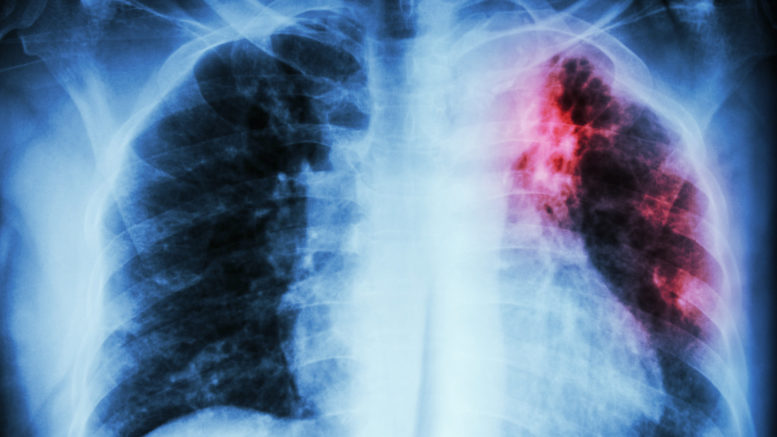

داء السل في المغرب.. حقوقيون يدقون ناقوس الخطر

في ظل الأرقام المقلقة التي أعلنت عنها وزارة الصحة والحماية الاجتماعية بمناسبة تخليد اليوم العالمي لمكافحة داء السل، حذرت الشبكة المغربية للدفاع عن الحق في الصحة والحق في الحياة من تدهور مقلق للوضع الوبائي المرتبط بداء السل في المغرب، مؤكدة أن هذا المرض يتسبب في وفاة نحو تسعة أشخاص يوميا، محملة السياسات العمومية مسؤولية ما وصفته بانتهاك الحق في الحياة.

وبمناسبة اليوم العالمي لمكافحة مرض السل، أطلقت الشبكة الحقوقية نداء حقوقيا اعتبرت فيه أن استمرار حصد الأرواح بسبب مرض “قابل للشفاء” يعكس اختلالات عميقة في السياسات الاجتماعية والاقتصادية، التي تساهم في توسيع الفوارق وتغفل المحددات الاجتماعية للصحة.

واعتبرت الشبكة، أن انتشار السل لا يرتبط بعوامل حتمية، بل هو نتيجة أوضاع اجتماعية صعبة تتسم باتساع الهشاشة والفقر.

وأشارت في بيان لها، إلى أن السكن غير اللائق، خاصة دور الصفيح والمساكن المكتظة التي تفتقر للتهوية، يشكل بيئة مناسبة لانتشار العدوى، إلى جانب سوء التغذية الذي يضعف المناعة في ظل ارتفاع أسعار المواد الغذائية وتراجع القدرة الشرائية.

وأوردت، أن المغرب يسجل سنويا ما بين 3000 و3300 وفاة بسبب داء السل، أي بمعدل تسع وفيات يوميا، مع بلوغ نسبة الوفيات حوالي 10 في المائة من مجموع المصابين، وارتفاعها إلى نحو 20 في المائة لدى المصابين بالسل وفيروس نقص المناعة البشرية (السيدا) في الوقت نفسه.

إلى جانب ذلك، نبهت إلى التناقض بين الالتزامات الدولية للمغرب الرامية إلى القضاء على السل في أفق 2030، والواقع الذي يشهد تسجيل أكثر من 37 ألف حالة جديدة سنويا، مع وجود نسبة تقدر بحوالي 15 في المائة من الحالات غير المكتشفة.

وفي نفس السياق، أشارت إلى اختلالات في منظومة الوقاية والتشخيص، خاصة في الأحياء الشعبية والمناطق النائية التي تعاني من نقص الوسائل التقنية، مما يؤدي إلى بقاء عدد من الحالات خارج مسار العلاج، في ظل استمرار الفوارق المجالية وارتفاع الإصابات لدى الفئات الأكثر عرضة، مثل المدخنين ومدمني المخدرات والمصابين بفيروس نقص المناعة، مع غياب استراتيجيات وقائية مدمجة.

واعتبرت الشبكة أن تدبير الأدوية يطرح إشكالات خطيرة، مبرزة أن احتكار الدولة لأدوية السل وعدم توفرها بشكل منتظم داخل المؤسسات الصحية يؤدي إلى انقطاعات متكررة، وهو ما يفاقم معاناة المرضى ويساهم في ظهور حالات مقاومة للعلاج.

وفي هذا الصدد، دعت الشبكة إلى إخضاع ميزانيات برامج محاربة السل لافتحاص من قبل المجلس الأعلى للحسابات، والعمل على تأمين مخزون استراتيجي دائم من الأدوية وتوفيرها مجانا دون انقطاع، إلى جانب تحديث وسائل التشخيص، ومعالجة العوامل الاجتماعية المرتبطة بالمرض، من سكن وتغذية وفقر، مع التشديد على ضرورة التصدي لانتشار المخدرات.